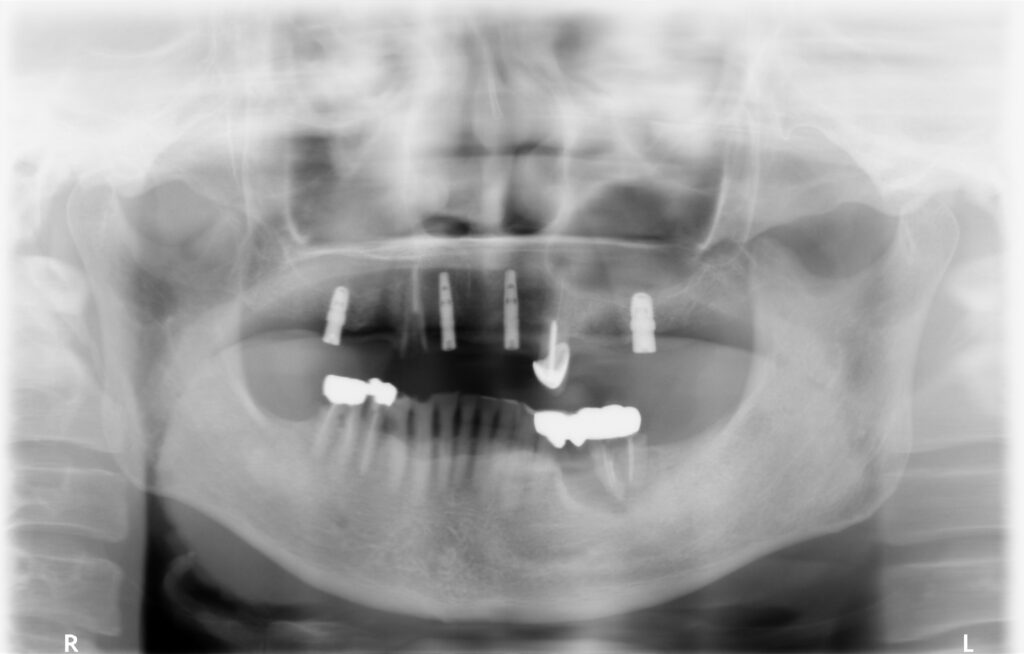

■治療中の処置

▼上顎

実際には抜歯が必須ではない歯もありましたが、噛み合わせの平面を整えたうえで総義歯を管理しやすくするため、相談のうえで抜歯を選択。

その後、上顎に2本のインプラントを埋入しました。

▼下顎

過去にブリッジ治療が行われていた部分を撤去し、インプラント治療へ変更。

骨が不足していたため、骨移植(GBR)を併用しています。

1.欠損部位(上下顎)のインプラント治療

2.上顎をインプラントオーバーデンチャーへ変更